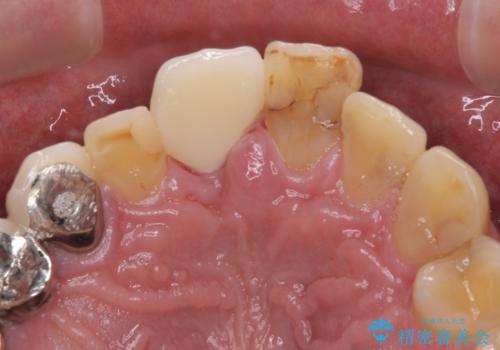

補綴治療としては、インプラントあるいはブリッジの2つがありますが、患者様と相談した結果、インプラントによる補綴治療を選択することとなりました。

咬合力が非常に強いため、インプラントにも過度な力の負担が発生する恐れがあります。

長期間安定して使用いただくために、睡眠時のマウスピースの装着による咬合力の分散が必要となります。